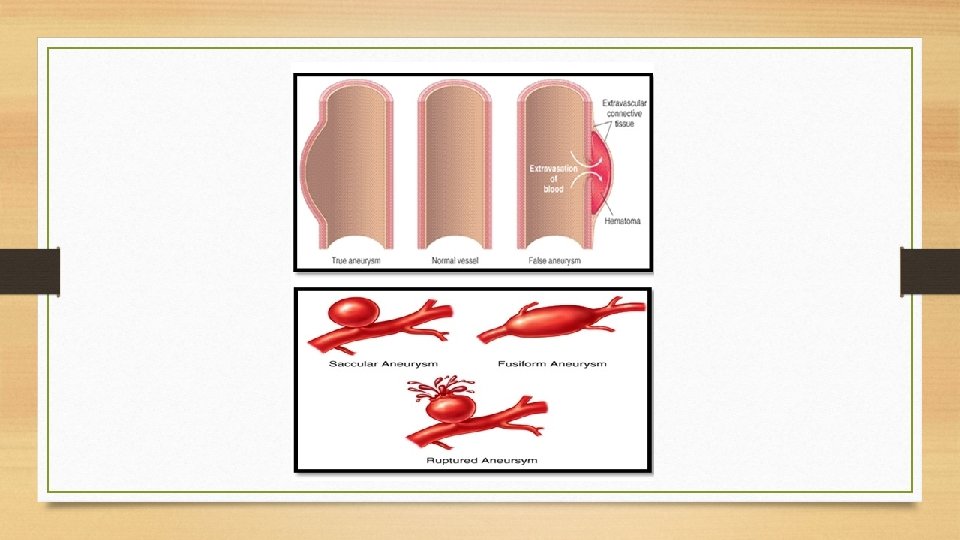

Definition: An aneurysm is defined as a permanent abnormal dilatation of a blood vessel occurring due to congenital or acquired weakening or destruction of the vessel wall.

Classification: Aneurysms can be classified on the basis of various features: A. Depending upon the composition of the wall: 1. True aneurysm: composed of all layers of a normal vessel wall. 2. False aneurysm: having fibrous wall and occurring often from trauma to the vessel. B. Depending upon the shape: 1. Saccular having large spherical out pouching. 2. Fusiform having slow spindle-shaped dilatation. 3. Cylindrical with a continuous parallel dilatation. 4. Serpentine or varicose which has tortuous dilatation of the vessel. 5. Berry aneurysms which are small dilatations especially affecting the circle of Willis in the base of the brain. C. Based on pathogenic mechanisms: 1. Atherosclerotic (arteriosclerotic) aneurysms are the most common type. 2. Syphilitic aneurysms found in the tertiary stage of the syphilis. 3. Dissecting aneurysms (Dissecting Hematoma) in which the blood enters the separated or dissected wall of the vessel. 4. Mycotic aneurysms which result from weakening of the arterial wall by microbial infection. The three common types of aortic aneurysms, atherosclerotic, syphilitic and dissecting, are described below.